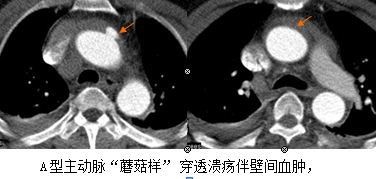

主动脉夹层(AD)是指主动脉腔内的血液从主动脉内膜撕裂口进入主动脉壁内,使主动脉壁中层形成夹层血肿,并沿主动脉纵轴扩展的一种心血管系统的灾难性疾病,主动脉是身体的主干血管,承受直接来自心脏跳动的压力,血流量巨大,一旦出现内膜层撕裂,破裂的机会非常大,死亡率也非常高。那么主动脉壁内血肿及主动脉穿透性溃疡也高危吗?漯河市中心医院普外二血管外科团队近10年已经成功治愈300多例急性主动脉综合征,近日我们科连续收治了3例主动脉壁内血肿及主动脉穿透性溃疡患者,那么它是不是风险明显减小,死亡率明显降低呢?下面就这3个病人的转归解读一下。

三位患者均以突发急性胸痛入急救中心,在急救中心做主动脉CTA检查明确诊断,其中2例女性患者同时合并全主动脉壁间血肿及多发穿透性溃疡,1例男性患者诊断全主动脉壁间血肿。

三例病人均在常规严密监护下精心治疗,适时选择手术时机。两例患者比较平稳,三周后,虽然血肿明显缩小,但是有的溃疡灶变大、有的形成小夹层,也应该手术,所以三周后顺利成功行介入覆膜支架植入手术。另一例男性患者,入院后病情趋于稳定,第4天时感到明显好转,但在正常排便时,突然病情加重,急查CTA血肿变逆撕为A型夹层,明确病情更加凶险,趋于破裂,急转胸外科,开胸手术,所幸抢救成功,保住了性命。可见壁内血肿,穿透性溃疡,同主动脉夹层一样,同样具有高风险。